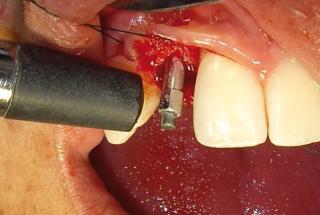

Clinical cases

MPI closely monitors clinical cases in the market to ensure their correct functioning and successful outcome.